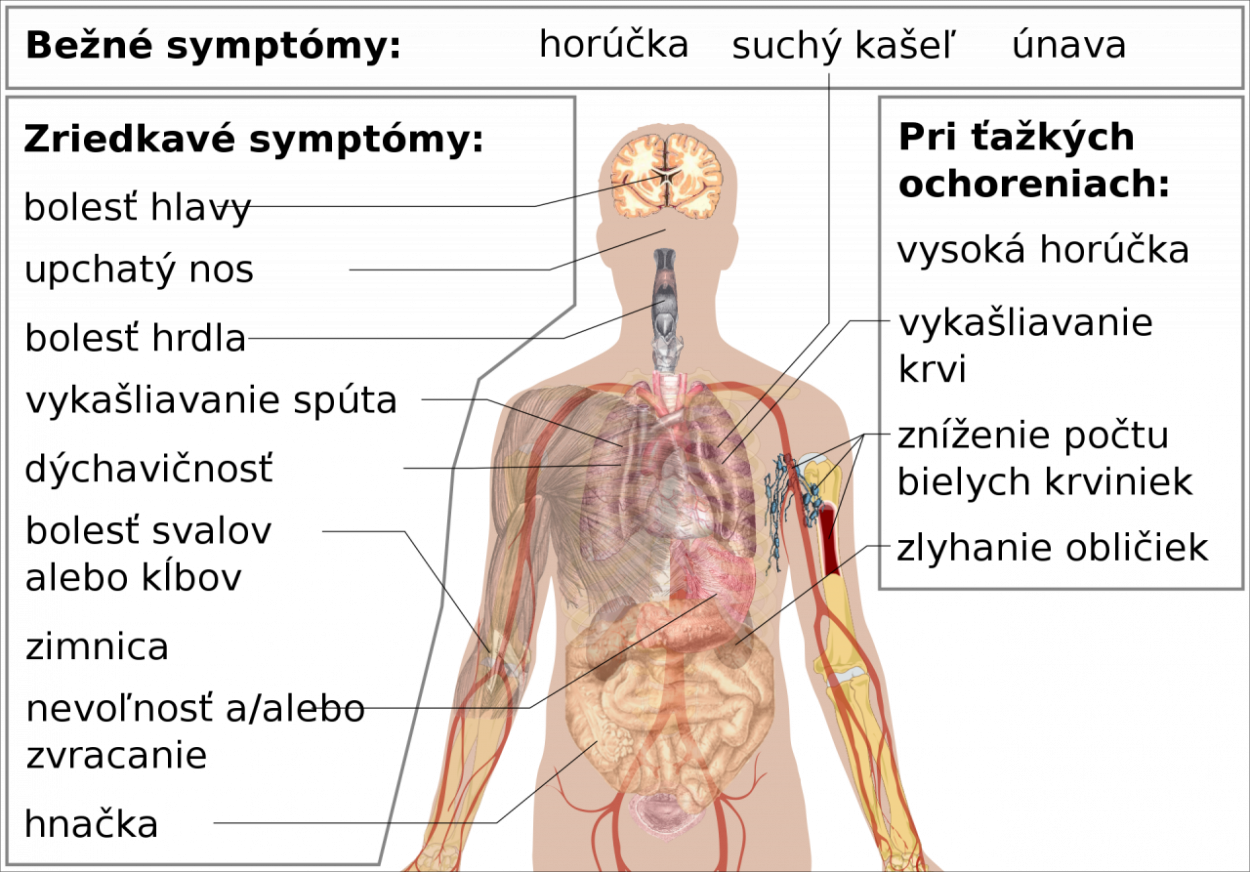

podľa WHO sú symptómy infikovaných detí a adolescentov miernejšie ako u dospelých. Z tradičného zoznamu symptómov – horúčka, suchý kašel a únava – majú často len jeden alebo dva, prípadne sa cítia mierne oslabene, pociťujú sucho v ústach alebo kýchajú.

Pri mladších deťoch je priebeh spravidla mierny, niekedy sprevádzaný krátkou epizódou hnačiek alebo zvracania.